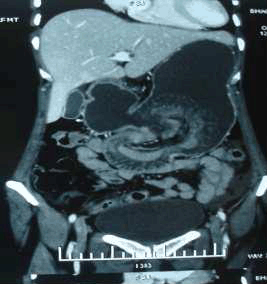

A 50-year-old female patient presented to ESI-PGIMSR with complaints of acute abdominal pain, vomiting and mass in the upper abdomen since four days. She had undergone gastrojejunostomy and truncal vagotomy for chronic duodenal ulcer twenty years back. On physical examination, the patient was dehydrated with pulse rate of 108/minute, blood pressure of 100/60 mmHg and respiratory rate of 18/min. Abdominal examination revealed upper midline abdominal scar of previous laparotomy. A tender sausage shaped lump was palpable in the umbilical region measuring 10x5 cm which moved with respiration (figure 1). Laboratory investigations showed hemoglobin of 9.3 gm%. After correction of dehydration and electrolyte imbalance, an emergency upper gastrointestinal endoscopy was carried out which revealed an intussusception of small bowel at gastro-jejunal anastomosis (figure 2). Computed tomography (CT) scan of the abdomen and pelvis revealed retrograde jejuno-gastric intussusception through previous gastrojejunostomy with edematous walls of intussusception and minimal ascites (figure 3). After initial treatment with intravenous fluids, nasogastric suction and antibiotics, emergency exploratory laparotomy was carried out.

Figure 3: CT scan of abdomen showing dilated stomach with intragastric non homogeneous mass compatible with small bowel loops.